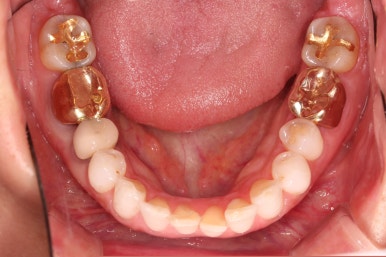

부가적으로 아랫니 앞니가 마모가 심하여 높낮이가 달라보이는 점이었는데요.

아래 앞니는 부분교정까지는 원하지 않으셔서 약간 다듬어 드리고 종료했습니다.